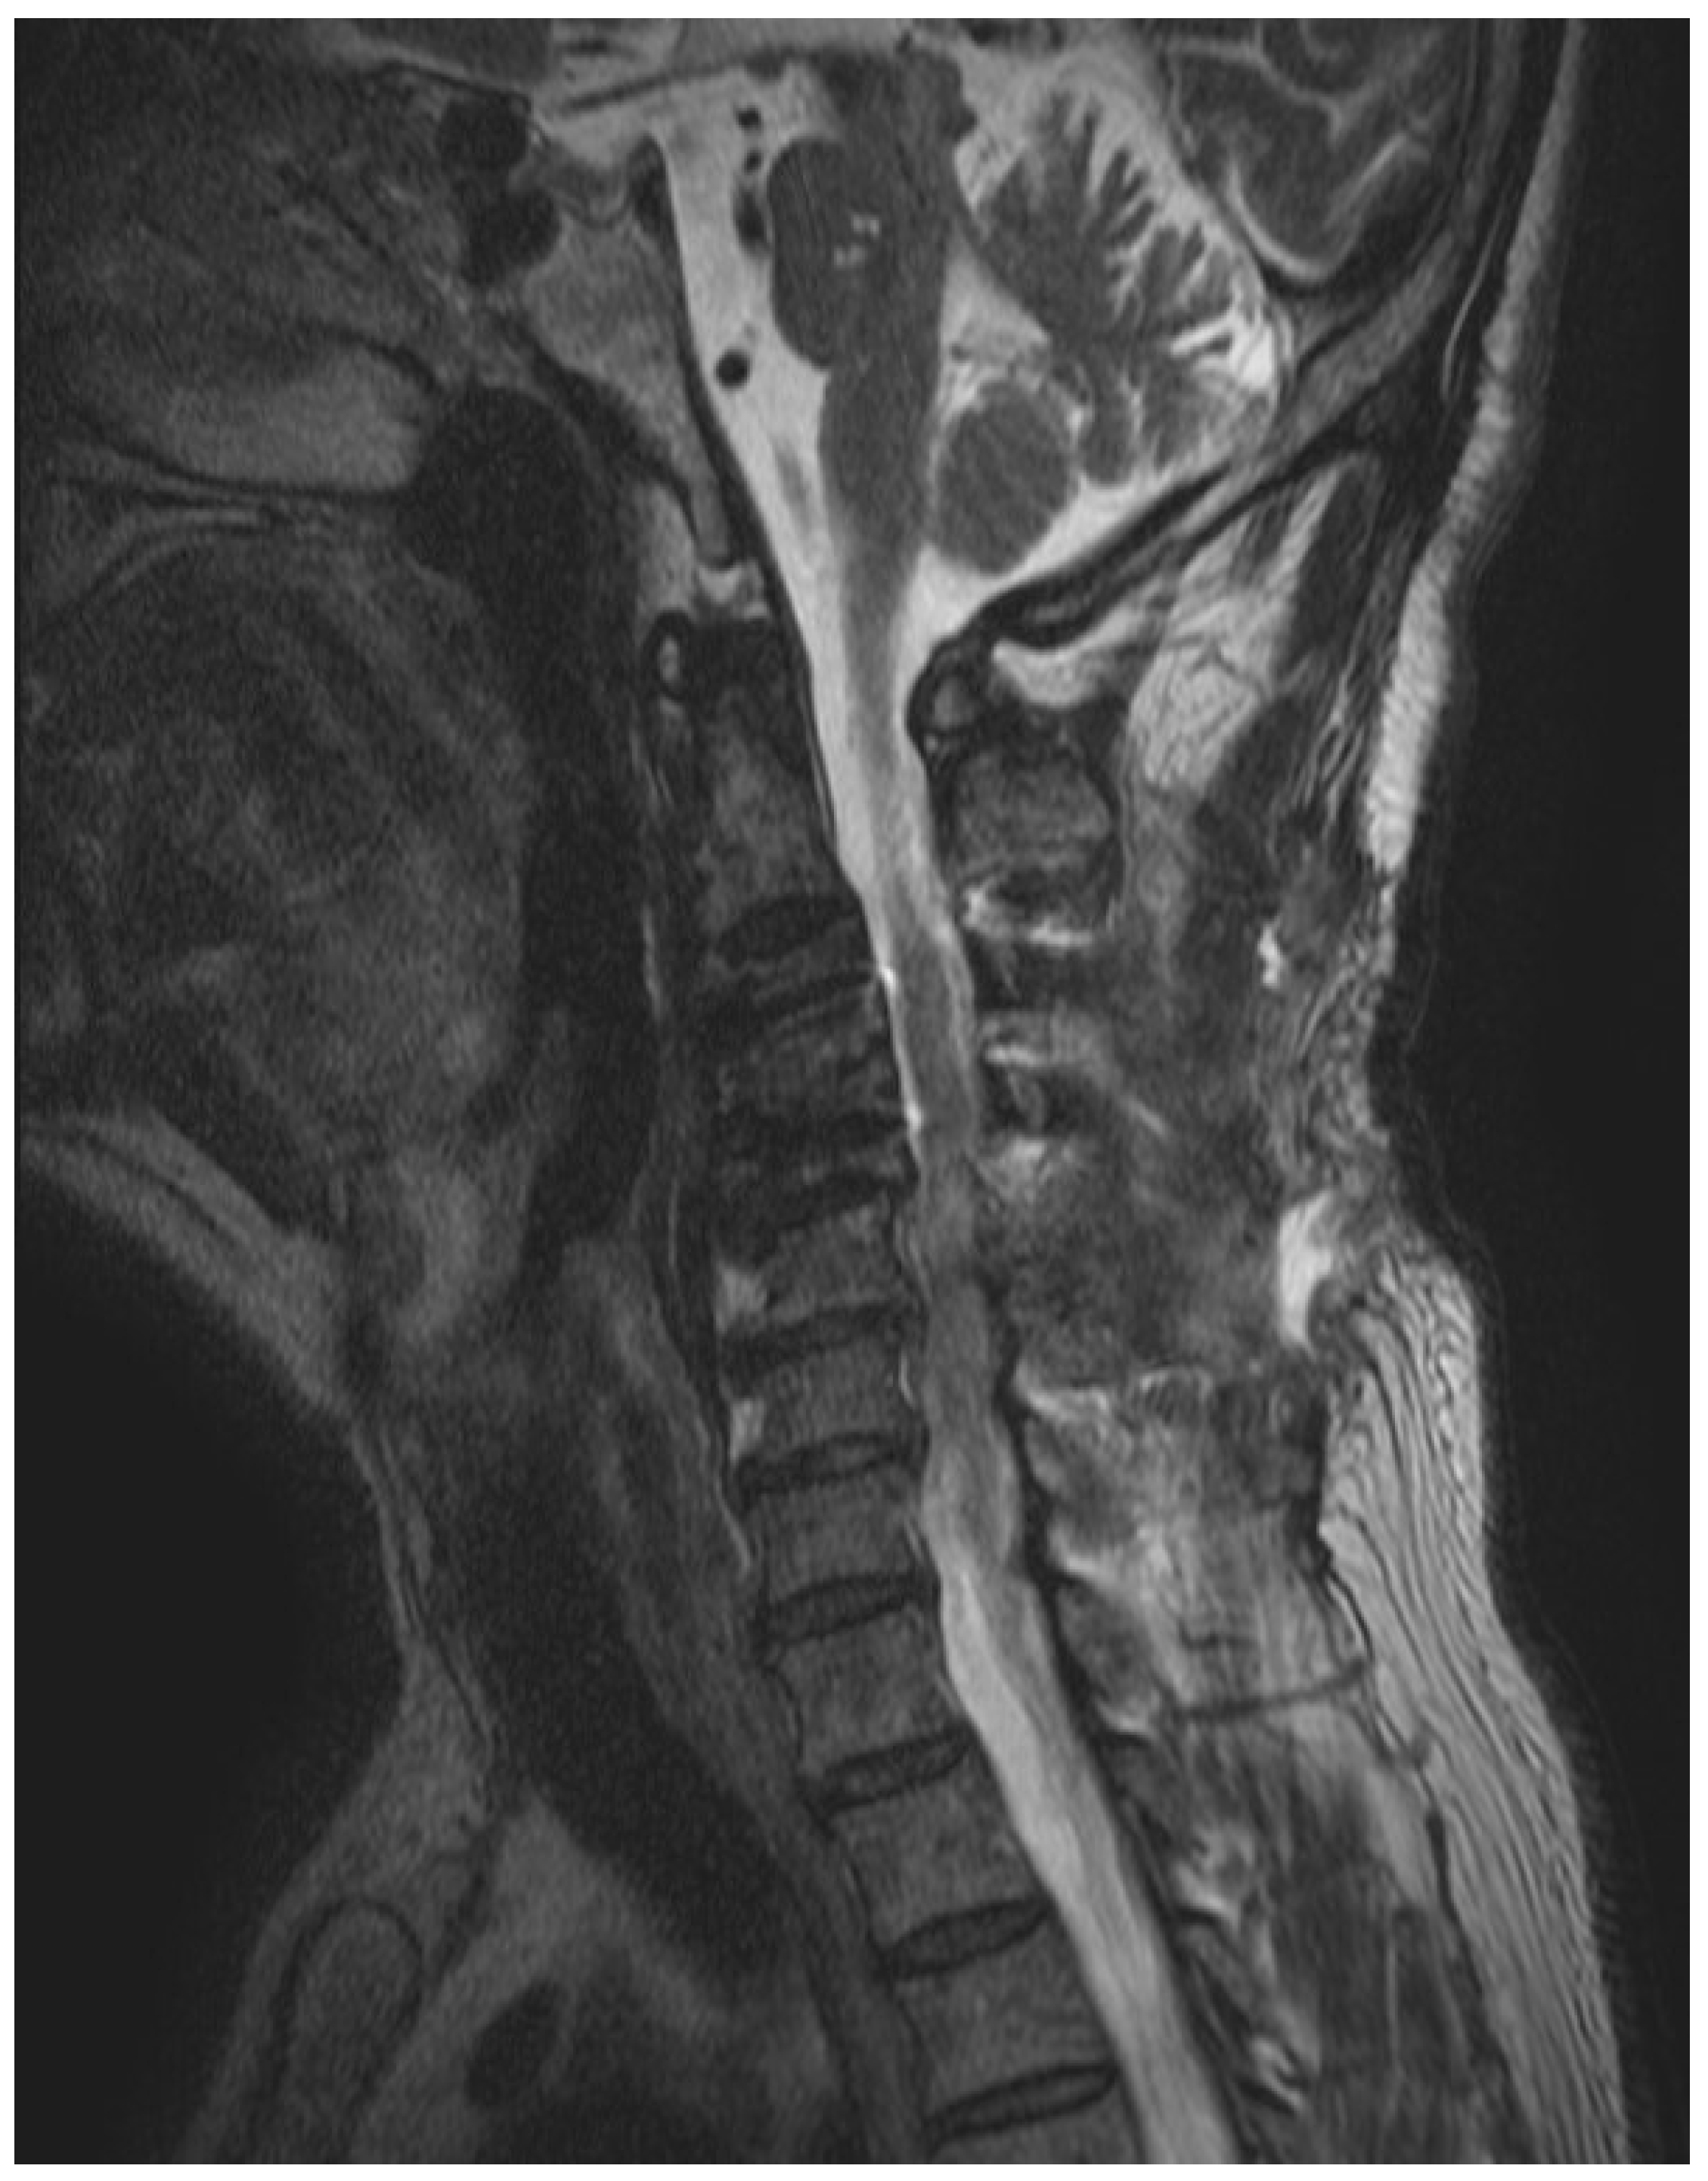

2. Case Presentation